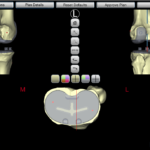

- Μέσα από την ανάλυση των εικόνων αρχικά εκτιμάται η διαταραχή του άξονα ολόκληρου του σκέλους σας. Όπως αναφέρθηκε προηγούμενα, η φθορά έχει προκαλέσει ασυμμετρία και έχει “στραβώσει” το γόνατό σας. Η διόρθωση είναι πολύ σημαντική. Ο άξονας της άρθρωσης αν είναι σωστός εξασφαλίζει ότι τα φορτία θα διανέμονται ομοιόμορφα στο τεχνητό γόνατο που θα σας τοποθετηθεί. Αυτό είναι απαραίτητο τόσο για τη σωστή λειτουργία του όσο και για τη διάρκεια στο χρόνο. Οι ακριβείς μοίρες διόρθωσης εκτιμώνται με τη μέθοδο αυτή με μεγάλη αξιοπιστία. (εικόνα 9 ).

- Το γόνατό σας αναπαριστάται τρισδιάστατα με εκπληκτική ακρίβεια. Το οστό που έχει φθαρεί, η παρουσία οστεοφύτων (που έχετε ακούσει ως “άλατα”) περιγράφονται με λεπτομέρεια (εικόνα 10 και εικόνα 11).